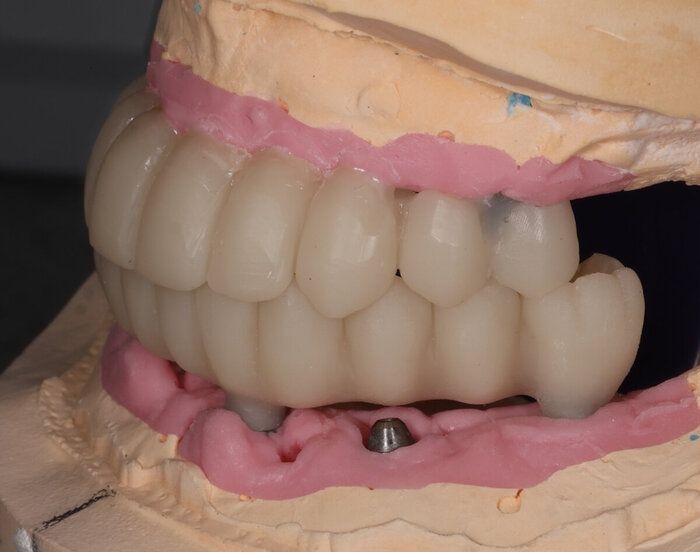

А вот как выглядел наш любимый, быстрый воск:

Постановка на воске

Разница - в первом варианте зубы не из стандартного набора, а те, что пациенту подходят больше. С этим прототипом можно даже пожить какое-то время, попривыкать к нему. Понять, что нравится, а что не особо.

Получилось так, что сверху всего 8 зубов, по 4 с каждой стороны. Чёрная точка (которую вы точно увидите, скос эмали на зубе 1.1) - конструктивные особенности, всё это будет закрыто пломбировочным материалом. Зуб 1.1 - дополнительный имлантат, который потом планируем убрать. Он нужен лишь для усиления, ибо торк полноценный был получен только на одном из остальных 6-ти установленных.

Напоминаю - протезы временные адаптационные

Так же важный момент - верхний протез соприкасается с нижним только в точках полученного торка (их всего 2), остальное "на весу" и жевать не способно.

Рекомендации - мягкая, жидкая пища 4 месяца! Это важно.

Низ - всё ок.